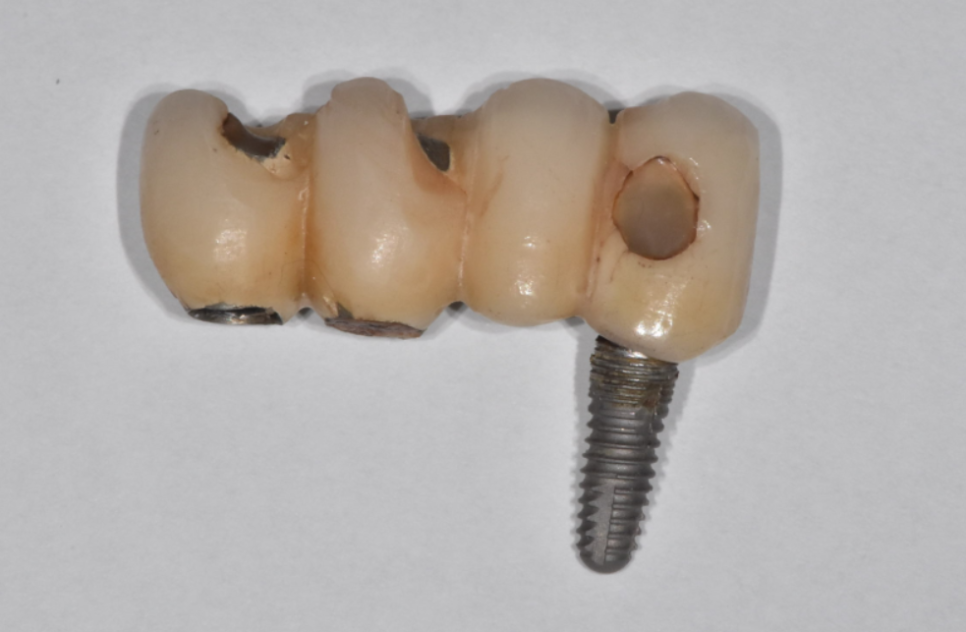

그럼 임플란트를 다시 수술해야하는데

처음 했던것과 달리

한번 했던 곳을 또 하는것이기 때문에

난이도가 올라가게 됩니다.

수술이 쉽지 않다는 얘기!!